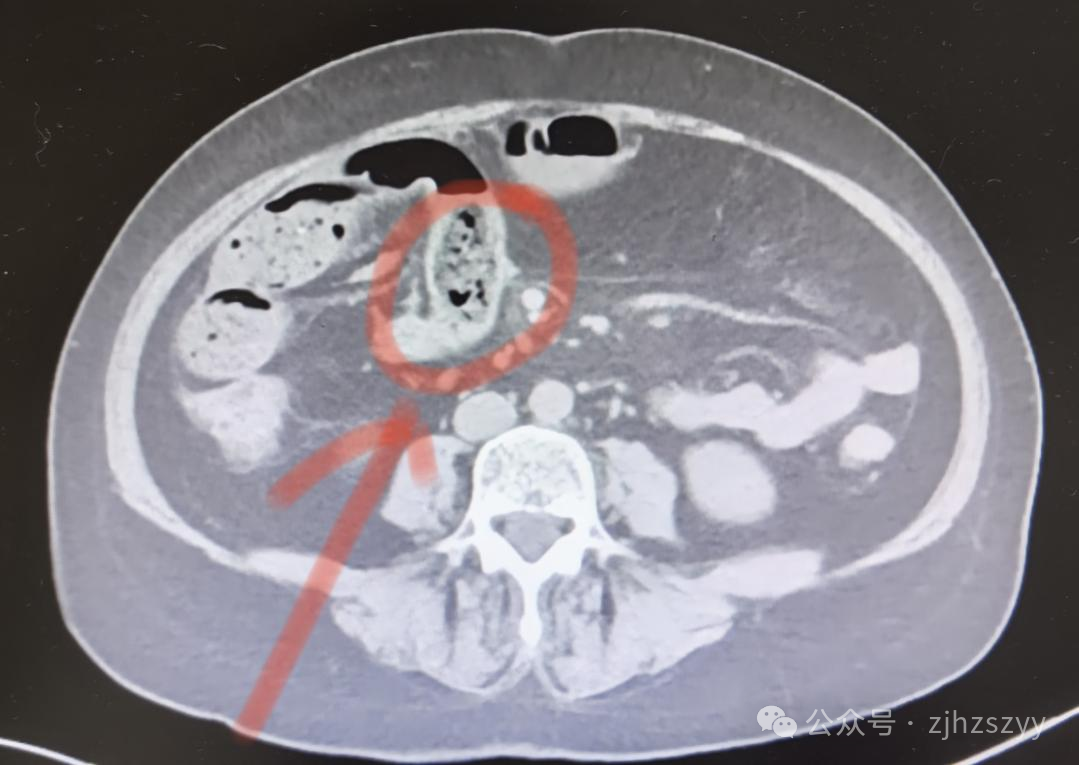

这是因为柿子中含有较多的鞣酸和果胶,在胃酸的作用下,鞣酸可与蛋白质结合,形成分子较大且不溶于水的鞣酸蛋白,再与其他食物残渣凝结成块,越积越大就会形成“柿石”。

➤“柿石”在胃内不断摩擦,可能使人出现腹胀、胃痛、恶心、呕吐等症状。

➤ 如果“柿石”进入肠道又无法顺利排出,则可能导致肠梗阻,严重者会引发肠坏死,甚至引起弥漫性腹膜炎而危及生命。